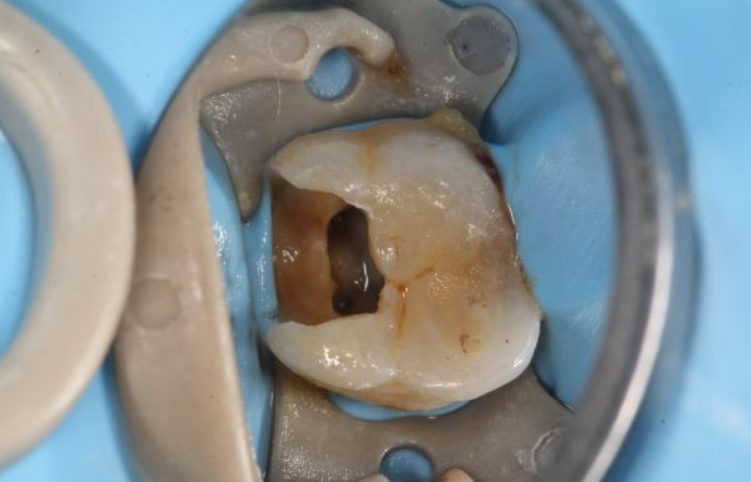

主诉 病史 下后牙夜间痛两天,冷热刺激

下颌第一磨牙远中3根管再治疗1例

一例根管治疗